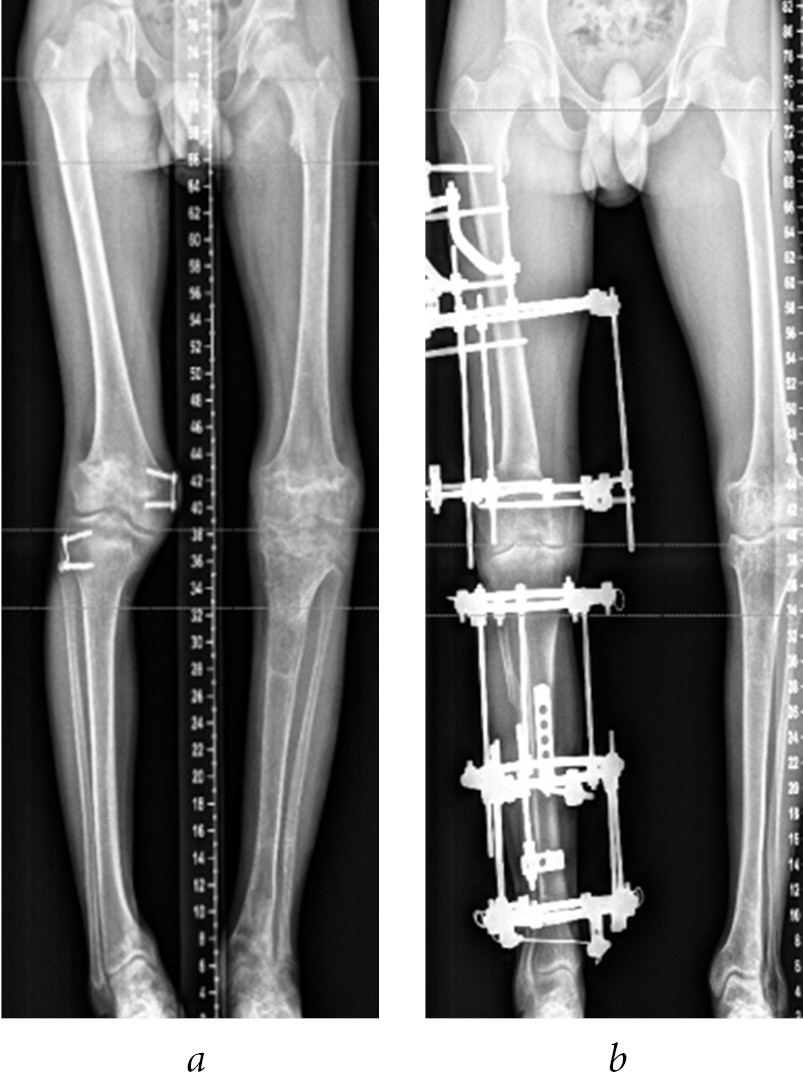

In 2014, the first stage was a superimposition of a wire-rod apparatus on the right thigh and lower leg and osteotomy of the right femur in the lower third tibia, and fibula in the upper third was performed (Fig. 8).

Fig. 8. Radiographs (a–c) and photograph (d) of patient K. before (a), during (b), and after the completion (c and d) of correction of the right lower limb deformity

In 2015, a wire-rod apparatus was placed on the left lower leg, and osteotomy of the lower leg bones in the upper third was performed (Fig. 9). Epiphysiodesis of the remaining functioning sections of the distal femoral and proximal tibia of the right lower limb was not performed.

Fig. 9. Radiographs of the lower limbs of patient K. before (a) and during (b) the correction of deformity of the left lower limb